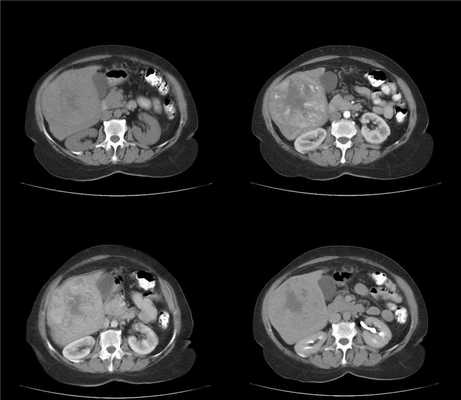

(Справа) На фотографии среза удаленной печени визуализируются узлы и цирротические изменения, а также участок сливного фиброза бледно-желтого цвета с ретракцией капсулы над ним. Передний и медиальный сегменты непропорционально изменены, при этом латеральный сегмент и хвостатая доля относительно сохранны. (Слева) На КТ в артериальной фазе контрастного усиления определяется, что образование минимально накапливает контраст, однако имеется подозрение на наличие сгруппированных и деформированных ветвей печеночной артерии.

(Справа) На КТ в отсроченной фазе контрастного усиления у этого же пациента определяется персистирующее повышенное накопление контраста сливными участками фиброза. Обратите внимание на варикозно расширенные вены, расширение фиссур, а также увеличение селезенки (признаки цирроза).

(Слева) На аксиальной КТ без контрастного усиления определяется изменение морфологии печени, обусловленное циррозом, на фоне асцита. Также визуализируется гиподенсное образование (сливной фиброз), обусловливающее ретракцию капсулы, и асцитическая жидкость около него.

(Справа) На аксиальной КТ без контрастного усиления у этого же пациента определяется очаговый сливной фиброз в переднем и медиальном сегментах печени, обусловливающий ретракцию капсулы. Обратите внимание на уменьшение объема медиального сегмента, левый край которого отмечен межсегментарной бороздой. (Слева) На аксиальной Т1 ВИ МР томограмме определяется гипоинтенсивный очаг в переднем и медиальном сегментах печени с ретракцией капсулы над ними.

(Справа) На аксиальной Т2 ВИ МР томограмме у этого же пациента визуализируется гиперинтенсивный участок сливного фиброза. Изменения в виде фиброза и уменьшения объема затрагивают лишь передний и медиальный сегменты печени. Обратите внимание на асцитическую жидкость в околопеченочном пространстве. (Слева) На аксиальной КТ без контрастного усиления на фоне асцита и увеличения селезенки визуализируется цирротически измененная печень с бугристыми краями. Определяется также обширный гиподенсный участок, занимающий практически всю правую долю печени, значительно уменьшенную в объеме, с ретракцией капсулы над ней.

(Справа) На аксиальной КТ в венозную фазу контрастного усиления у этого же пациента описанный выше участок в правой доле становится гиперденсным по отношению к остаткам паренхимы печени, что является признаком, типичным для распространенного фиброза. У этого пациента практически вся правая доля печени замещена сливными участками фиброзной ткани.

(Слева) На аксиальном КТ срезе (артериальная фаза) у женщины 60 лет, страдающей алкогольным циррозом печени, визуализируется клиновидный участок низкой плотности.

(Справа) На КТ в отсроченную фазу у этой же пациентки определяется персистирующее контрастное усиление участка сливного фиброза. Обратите также внимание на ретракцию капсулы над участком фиброза и асцит. (Слева) На аксиальной Т2 ВИ МР томограмме у мужчины 54 лет с алкогольным циррозом определяется измененная морфология печени, обусловленная циррозом, наряду с асцитом и спле-номегалией. Обратите внимание на клиновидный участок повышенной сигнальной интенсивности в переднем и медиальном сегментах (очаговый сливной фиброз).

(Справа) На аксиальной Т2 ВИ МР томограмме у этого же пациента определяется участок сливного фиброза. Объем пораженных сегментов печени уменьшен, что доказывает изменение положения желчного пузыряприлежащего к увеличенной реканализованной пупочной вене в межсегментарной борозде. (Слева) На аксиальной Т1 ВИ МР томограмме без контрастного усиления у этого же пациента визуализируется гипоинтенсивный участок (сливной фиброз) клиновидной формы с ретракцией расположенной над ним капсулы печени.

(Справа) На аксиальной Т1 ВИ МР томограмме в венозную фазу контрастного усиления у этого же пациента определяется минимальное накопление контрастного вещества участком фиброза. Реканализованная пупочная вена, проходящая в межсегментарной борозде, указывает на левый латеральный край фиброзно измененного, «сморщенного» участка печени.